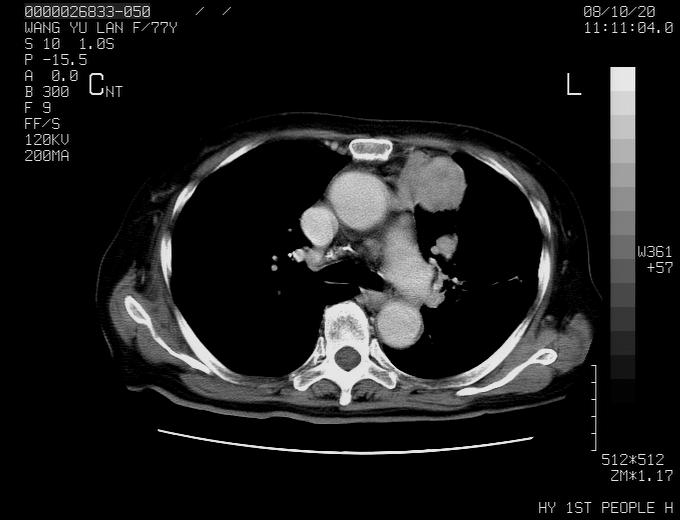

动脉期未见大血管同步强化,首先考虑周围型肺癌

动脉期病灶近中线侧可见星芒状与大血管同等强化密度,支持考虑血管畸形伴血栓形成,动脉期不曲型,不除外周围型肺癌

1、考虑avm可能性大。2、纵隔有肿大淋巴结,左肺上叶有炎性病变,不排除肺癌并转移可能。